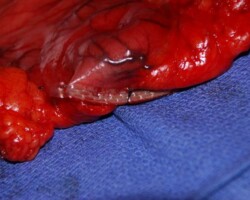

Resection of large retroperitoneal sarcoma including right and transverse colectomy and right hepatectomy